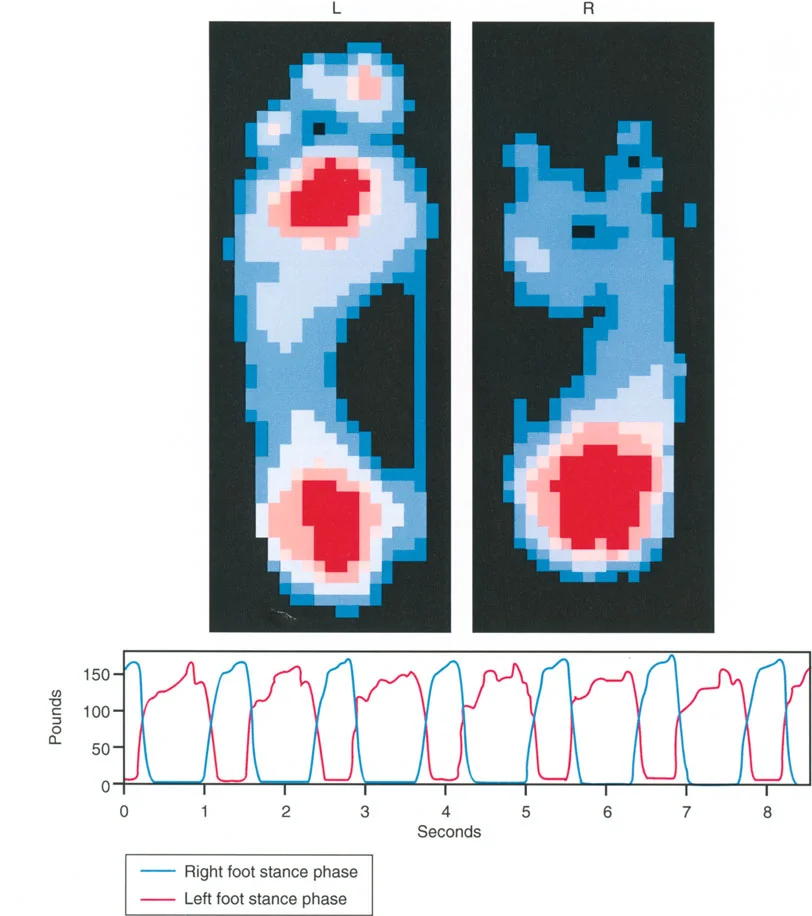

3. تحميل المفصل غير الطبيعي ومتجه رد فعل الأرض (GRV)

متجه رد فعل الأرض (Ground Reaction Vector - GRV) هو القوة المحصلة التي تؤثر بها الأرض على القدم عند نقل وزن الجسم أثناء الوقوف. يتم تحديدها بواسطة قانون نيوتن الثالث. في طرف سفلي متوافق تمامًا، يمر متجه رد فعل الأرض مباشرة عبر مركز مفاصل الورك والركبة والكاحل في كل من المستويين الأمامي والسهمي. وهذا يضمن توزيعًا متساويًا وفسيولوجيًا لقوى الضغط عبر الغضروف المفصلي.

تزيح تشوهات العظام متجه رد فعل الأرض بعيدًا عن مركز المفصل، مما يخلق عزم دوران مرضيًا.

أمراض المستوى الأمامي (التقوس/الفحج - Varus/Valgus):

إذا كان المريض يعاني من تشوه تقوس (Varus) في عظم الساق أو الفخذ، فإن متجه رد فعل الأرض يتحرك نحو الداخل (إنسيًا). كلما مر متجه رد فعل الأرض أكثر إنسيًا بالنسبة لمركز الركبة، زاد عزم دوران التقريب. وهذا يزيد بشكل كبير من قوى الضغط على الجزء الإنسي من سطح عظم الساق القريب (medial tibial plateau).

بينما يحمل الوقوف على ساق واحدة طبيعيًا الجزء الإنسي بحوالي 75%، فإن تشوه التقوس الشديد (الذي يسبب انحرافًا كبيرًا في المحور الميكانيكي، أو MAD) يمكن أن ينقل 100% من الحمل إلى الجزء الإنسي. على مدى فترات طويلة، يؤدي هذا التحميل الميكانيكي الموضعي المفرط إلى تدهور سريع وتدريجي للغضروف المفصلي، وتصلب تحت الغضروف، وتكون نتوءات عظمية، وفي النهاية إلى التهاب مفصل الركبة في مراحله المتأخرة.